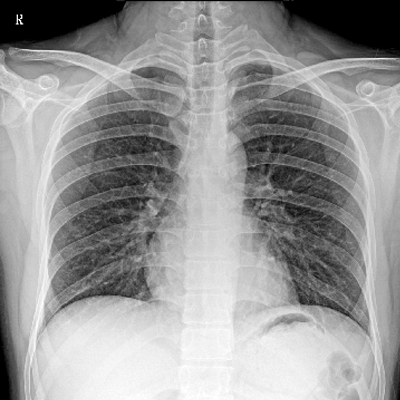

● 數(shù)字化無(wú)線平板成像,操作簡(jiǎn)便,成像質(zhì)量高